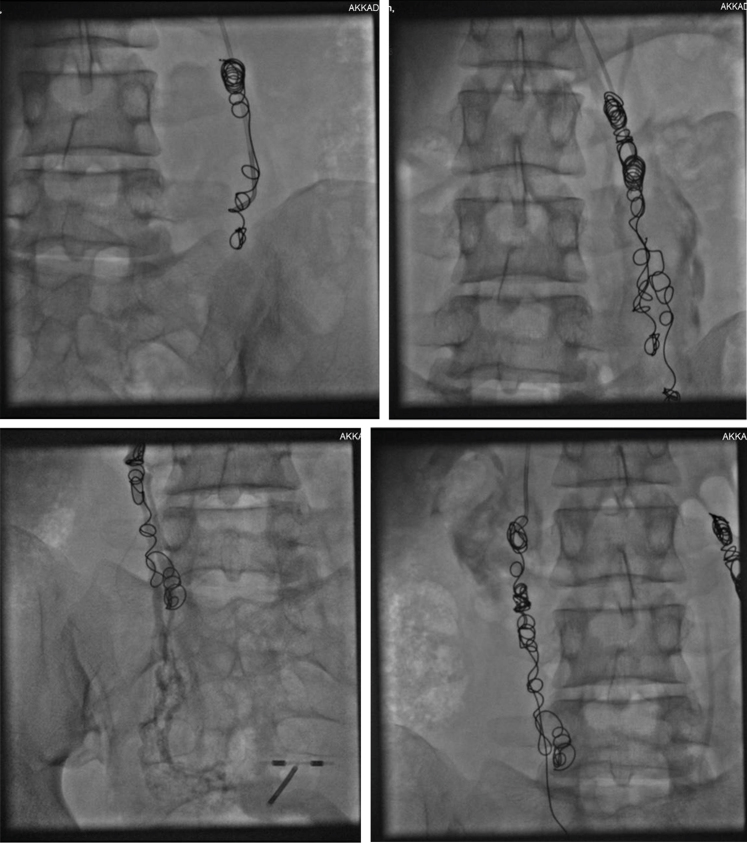

This is a retrospective study in which we compared using metallic coil combined with sclerosant foam and N-butyl-2-cyanoacrylate in female patients with PeVD in terms of clinical and technical success as well as safety. Adult patients with symptoms suggestive of primary PeVD and confirmed with Doppler ultrasound examination and/or venography were eligible for the study. Secondary PeVD and lost follow-up were excluded.

This study included 167 patients who were treated with coil and sclerotherapy (n = 87; group I) or N-butyl-2-cyanoacrylate (n = 80; group II) embolization. Immediate postoperative veins’ closure was achieved in all patients in the two groups. At the 6-month follow-up, there was a statistically significantly higher occlusion rate in group I (100% compared with 93.8% in group II, P = .018) with five new cases of recanalization. The 6-month visual analog scale score was lower in group I (median of 1 and mean of 1.14 ± 0.904) than group II (median of 2 and mean of 1.7 ± 1.32), with a statistically significant difference (P = .005).

The study emphasizes the potential advantages of the sclerosant foam and metallic coil combination in achieving favorable outcomes for patients with PeVD.